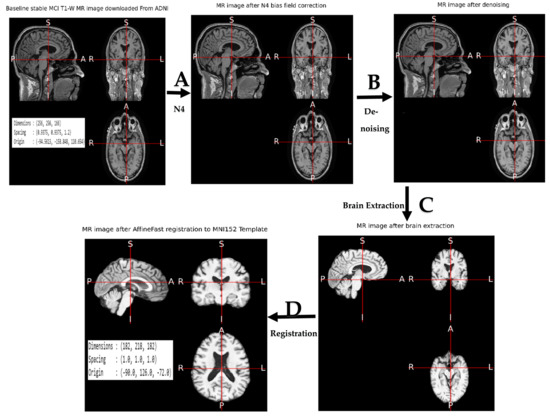

The baseline MRI scans were downloaded in the Neuroimaging Informatics Technology Initiative (NIfTI) [86] format from the ADNI and IXI databases. NIfTI is an upgraded version of the Analyze file format, which was created to be easier to use than DICOM while keeping all of the necessary information. It also has the advantage of storing a volume in a single file, with only a basic header followed by raw data. This allows it to load and process quickly. The ANtsPyNet [79] utilities were used to perform a standard preprocessing procedure on each image. The Advanced Normalization Tools (ANTs) pipeline [87,88,89] was employed. As illustrated in Figure 2, the implemented preprocessing pipeline included (A) N4 bias correction, (B) denoising, (C) brain extraction, and (D) affine registration to MNI152 template. The N4 bias field correction technique [90] is a widely used approach for correcting low-frequency intensity non-uniformity, often known as a bias or gain field, in MR image data. This strategy relies on a basic parametric model with no tissue classification. N4 bias correction of MR images was performed using the ants.utils.n4 bias field correction() [91] function, which was followed by denoising. Denoising’s [92] main purpose is to estimate the original image by suppressing noise in a noise-contaminated version of the image. Image noise may be created by a variety of internal and extrinsic factors that are difficult to prevent in real-world settings. As a result, picture denoising is significant in image classification, where recovering the original image content is critical for good results. In our work, denoising was performed in two steps: first, we added different intensities of salt and pepper noise [93,94] to the MR image and then we removed the noise using a spatially adaptive filter initially proposed by Manjon et al. [95] through ants utility ants.denoise_image() [96], which was followed by brain extraction. Brain extraction was conducted on MR images using AntsPyNet’s brain extraction() [97] tool, which uses a 3D U-net model called brainy [98] and ANTs-based training data to achieve brain extraction. The key advantage of brainy is its ability to exploit interslice contextual information [99]. This model obtained a median Dice score of 0.97, a mean of 0.96, a minimum of 0.91, and a maximum of 0.98 on a validation dataset of 99 T1-weighted brain scans and their associated, binarized FreeSurfer segmentations [99]. In three seconds, this model could predict the brain mask for a volume of 256 × 256 × 256, independent of orientation. Predicting the brain mask of each picture took around five seconds with our implementation. It was followed by affine fast registration [100] in the MNI 152 template [101], a universal brain atlas template, utilizing the ANTsPy tool ants.registration() [102]. The goal of registration is to eliminate any spatial disparities across subjects in the scanner and to reduce translations and rotations from a standard orientation. This aids the subsequent classification’s accuracy. After registration, the dimensions were uniformly rescaled to 182 × 218 × 182 for CNN learning. This registered MR image was used to classify the various stages of AD. In our implementation, the preparation of one MRI scan took around two minutes.

Figure 2.

This illustration shows an example of sMCI MR image preprocessing implemented in our study. The original MR picture dimensions were 256 × 256 × 166, but the output MRI dimensions were altered to 182 × 218 × 182. The actions listed were performed in sequence. (A) N4 bias field correction, (B) denoising, (C) 3D U-Net used for brain extraction, (D) affine fast registration in the MNI152 template.